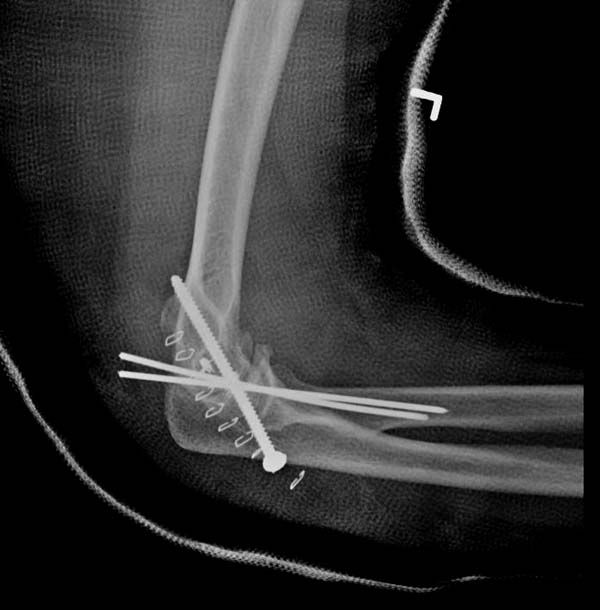

В данном случае имеется, так называемая, "ужасная триада" локтевого сустава, включающая перелом головки лучевой кости, перелом венечного отростка и вывих костей предплечья кзади, также в структуру травмы входит повреждение латерального коллатерального связочного комплекса и возможно передней порции медиальной коллатеральной связки. Лечение состоит из следующих этапов: фиксация венечного отростка( анкер или проволочная петля типа лассо), далее остеосинтез или протезирование головки лучевой кости ( КТ было бы желательно, фотографии не особо четкие), затем шов латерального коллатерального связочного комплекса. Если сохранится нестабильность, потребуется или шов передней порции медиальной коллатеральной связки с иммобилизацией верхней конечности аппаратом внешней фиксации (желательно с сохранением движений в локтевом суставе) или только аппарат(мнения расходятся). Аппарат 6 недель. Результаты лечения таких повреждений не очень хорошие.

Несмотря на отрицательный отзыв, некоторые нестабильные вывихи лечим трансартикулярным методом. Тонкие спицы ломаются и имеют риск внутрисуставной инфекции. Винты 3.5 мм не выдерживают, а более толстые каннюлированные винты неплохо проявили себя. Неосторожность при установке приводила к поломке тонких guide wire внутри сустава. Лучшие кортикальные в 4.5 мм и гипс на три недели. Винт удаляется, затем разработка сустава.

Иногда гипс не гарантировал стабильность и винт внутри гипса ломался. Удаление сломанного винта облегчаем, оставляя на пару мм длиннее с наружной стороны, Т.е винт через олекранон над наружный мыщелок, и никогда в трубку диафиза! Из малого разреза кончик сломанного винта удаляется без проблем.

Для примера здесь случай начатый в другом центре, а потом переправленный к нам.

Снимки: 1-2 вывих, 4-5 вторичное смещение в гипсе, реконструкция латеральной связки и капсулы 13-14, повторный вывих после реконструкции, перевод в наш центр; 18-21 временная фиксация, 22-25 трансартикулярная фиксация и нестабильная головка фиксирована спицами, 29-30 амбулаторно, 32-33 после удаления винта и спиц...